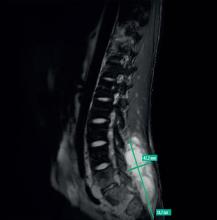

D’après : Bouvard B, Legrand E. Ostéoporose : encore trop ignorée ! Rev Prat Med Gen 2025;39(1100);381-91.